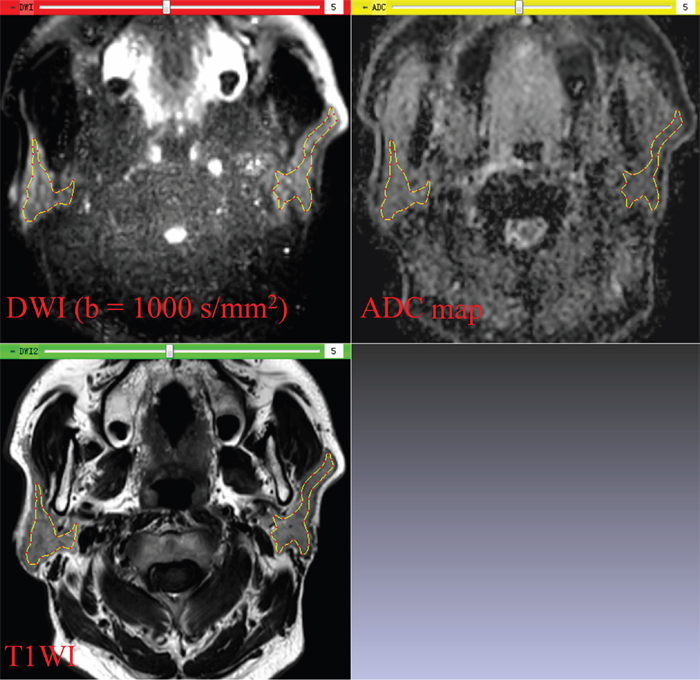

(2) Each ROI was drawn manually along the inner margin of the parotid glands on DW images, excluding visible retromandibular veins. Since DW images of parotid glands were acquired with the same slice thickness, slice gap, and field of view as T1-weighted images, the ROIs could be shown on the corresponding T1-weighted images and ADC maps in real time (Figure 2).

Figure 2: In-house software screenshot. The region of interest is exactly copied on the diffusion weighted image (DWI) to the corresponding T1-weighted image (T1WI) and apparent diffusion coefficient (ADC) map in real time. Parotid glands can be distinguished from the adjacent structures on DWI and T1WI.